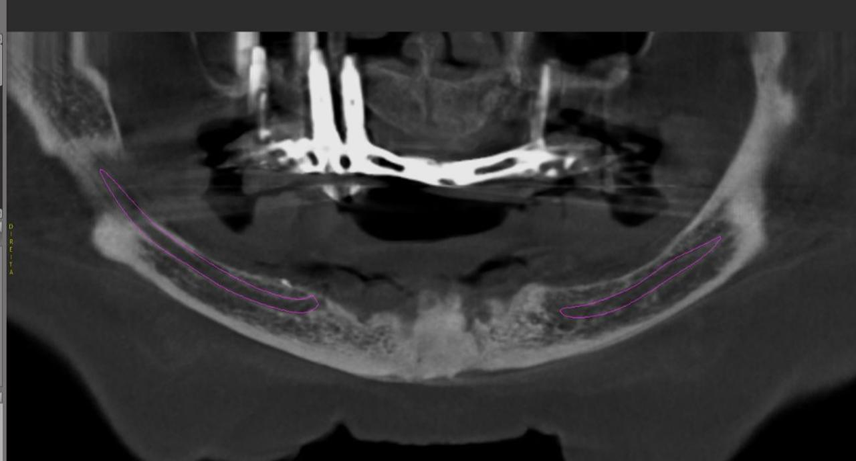

Paciente de 62 anos, do sexo feminino, sem comorbidades e história médica pregressa, apresentava severa reabsorção óssea em regiões anteriores e posteriores da mandíbula devido a uma peri-implantite (Figuras 1A e 1B). Feita a remoção dos implantes, a paciente optou por utilizar uma prótese total mucossuportada até a nova intervenção com prótese do tipo protocolo inferior. Após seis meses, a mandíbula encontrava-se cicatrizada (Figura 2). Como parte do protocolo diagnóstico, foi realizada tomografia computadorizada pela técnica do duplo DICOM. Com a severa perda óssea em região anterior de mandíbula, optamos por realizar a cirurgia de forma guiada, aumentando a previsibilidade e precisão da cirurgia. Os arquivos obtidos foram exportados para o software CoDiagnostiX, possibilitando a realização do planejamento reverso e o subsequente posicionamento virtual dos implantes (Figura 3). Com base no planejamento, optou-se pela instalação de quatro implantes Implacil Osstem CM AR Due Cone (3,5 x 7 mm), associados a mini-cônicos de 1,5 mm (Figuras 4A, 4B, 4C, 4D e 4E). A partir da tomografia da prótese da própria paciente, confeccionaram-se duas guias cirúrgicas: uma guia de pino de fixação (Figura 5) e uma guia de fresagem para a instalação dos implantes (Figura 6). Durante o procedimento cirúrgico, inicialmente foi posicionada a guia de pino de fixação para fresagem dos pinos de fixação e orientação da sequência cirúrgica (Figura 7). Após essa etapa, a guia foi substituída pela guia de fresagem dos implantes (Figura 8), utilizada para a fresagem e inserção dos implantes planejados (Figura 9). Concluída a instalação, optou-se por seguir o fluxo analógico, com a adaptação dos mini-cônicos 1.5 mm (Figura 10), realização da transferência de moldagem com silicona de adição leve e sutura com fio absorvível Vycril 6-0. O guia inicial foi adaptado com broca Maxicut, possibilitando sua utilização como molde de orientação para o laboratório protético (Figura 11). Após a moldagem, foram posicionadas as tampas de proteção sobre os implantes. Na fase protética, transcorridas 48 horas do procedimento cirúrgico, foi realizada a prova clínica da barra metálica e dos dentes (Figura 12). Na etapa subsequente, 72 horas após a cirurgia, procedeu-se à instalação e entrega do protocolo mandibular inferior e radiografia prévia, reabilitando funcional e esteticamente a paciente em curto espaço de tempo (Figuras 13A e 13B).